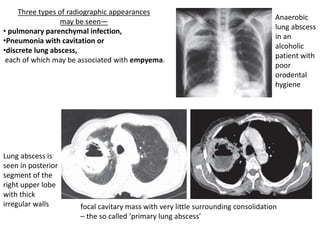

Three types of radiographic appearances

may be seen—

• pulmonary parenchymal infection,

•Pneumonia with cavitation or

•discrete lung abscess,

each of which may be associated with empyema.

Anaerobic

lung abscess

in an

alcoholic

patient with

poor

orodental

hygiene

Lung abscess is

seen in posterior

segment of the

right upper lobe

with thick

irregular walls focal cavitary mass with very little surrounding consolidation

– the so called ‘primary lung abscess’